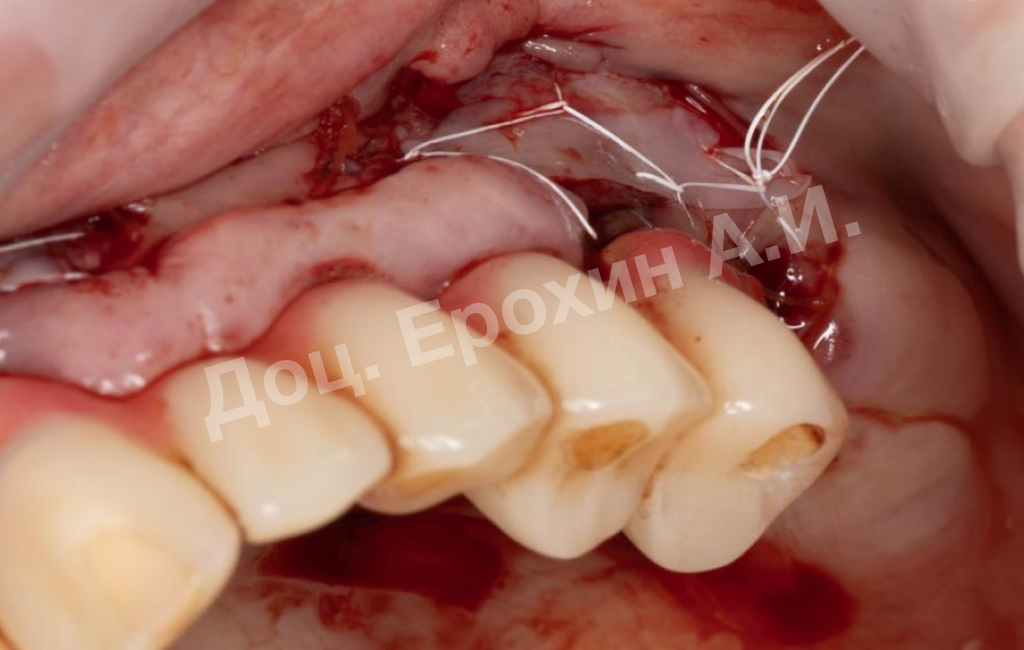

В результате, спустя 10 лет мы видим, что единственная часть десны в области имплантации, не затронутая рецессиями, — это зона, где была проведена трансплантация десневого фрагмента. С целью стабилизации имеющихся имплантатов на повторном приеме была проведена вестибулопластика по Кларку с фиксацией мягкотканных мукотомов, фрагментов эпителия с неба, зафиксированных швами.

В данном клиническом случае мы можем наблюдать эффект так называемого наползающего прикрепления (creeping attachment), когда десна после удаления момента натяжения начинает сама наплывать на ранее оголенные корни зубов и имплантаты.

На фото видно, что в первом сегменте с 2.5-3 мм оголение корня осталось меньше 1 мм, в области имплантата 21 рецессия самоустранилась, а в области имплантата 26 рецессия до операции была 4.5 мм, а после сократилась до 2 мм.